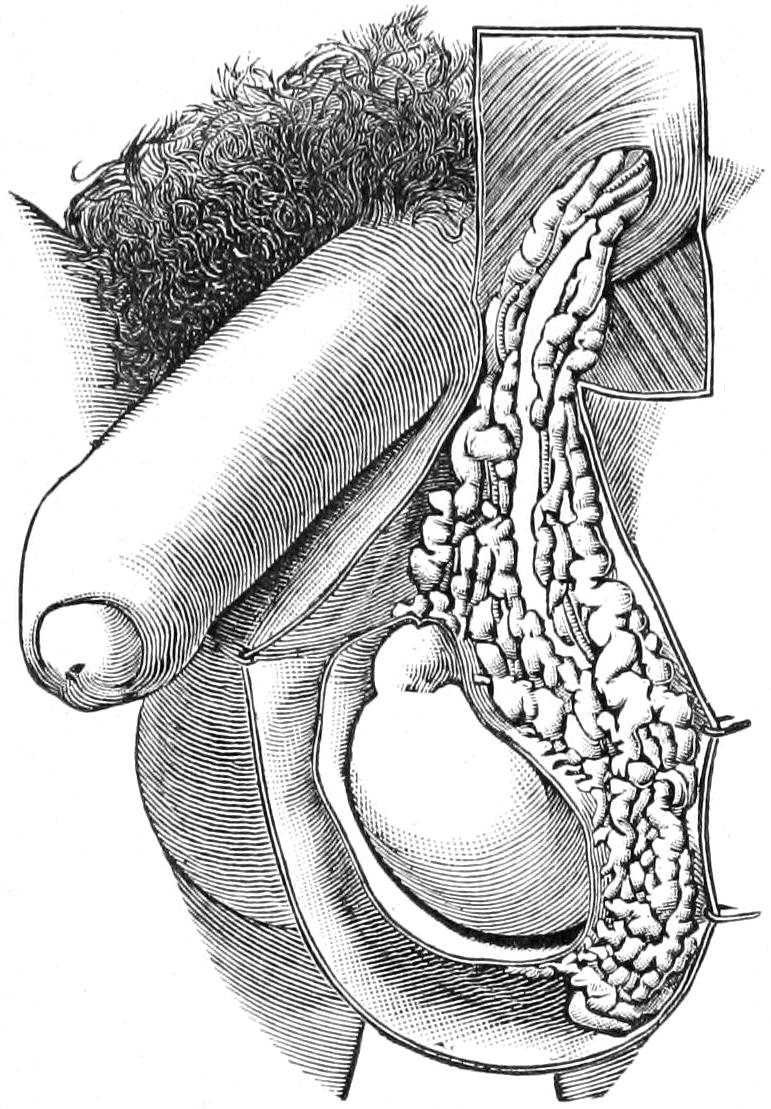

HERNIA 890